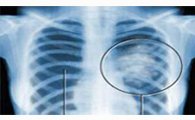

背景與目的 當肺癌瘤體較大時,形態常不規則, <全文>